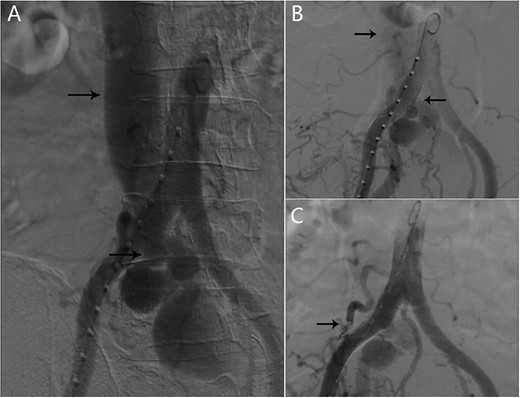

After multi-disciplinary team consideration, we decided to enclose the AVF by using covered stent at the right common iliac artery. Through a percutaneous right femoral approach, one covered stent graft (16–10–100 mm Medtronic) was implanted at the right common iliac artery. Angiography demonstrated that the contrast can pass into the inferior vena cava. We decided to embolized the lumbar artery by coils through the femoral approach to prevent the contrast passing into the venous system (Fig. 2). Completion angiography demonstrated a significant improvement. Symptoms alleviated quickly after successful endovascular treatment. One month later, left lower limb edema disappeared completely. After 12 months of follow-up, there were no complications occurred in the patient.

(A) AVF and inferior vena cava can be seen in the angiography; (B) one covered stent graft was implanted at the right common iliac artery; angiography demonstrated that the contrast can pass into the inferior vena cava; (C) after the lumbar artery was embolized by coils, inferior vena cava was no longer enhanced.